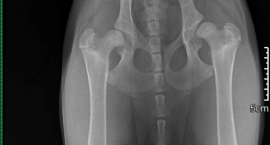

Badanie rentgenowskie wykazało, że Dejzi choruje na dysplazję stawów biodrowych, przy czym w lewej łapie stan ten jest już bardzo zaawansowany. Przy postępującej chorobie już za kilka miesięcy zwierzak nie będzie mógł chodzić, a każdy ruch okupiony będzie ogromnym bólem. Jedynym ratunkiem dla czworonoga jest operacja wymiany stawów biodrowych na implanty, która może być przeprowadzona w niemieckiej klinice weterynaryjnej. Ta jednak okazuje się być bardzo kosztowna.

- Już teraz chodzenie sprawia Dejzi straszny ból. Za pół roku, czyli w wieku ok 11 miesięcy, musi mieć przeprowadzoną operację, która najpewniej będzie wykonana w Niemczech. Co prawda można tak zabieg zrobić w Polsce, jednak u nas nie ma takich specjalistów i tego typu operacje są przeprowadzane bardzo rzadko. A u naszych zachodnich sąsiadów wstawienie takich implantów wykonywane jest praktycznie codziennie. To daje Dejzi znacznie większe szanse na powodzenie operacji. Sam nasz weterynarz polecił nam właśnie klinikę w Niemczech – mówi Emilia Sikora, właścicielka suczki.